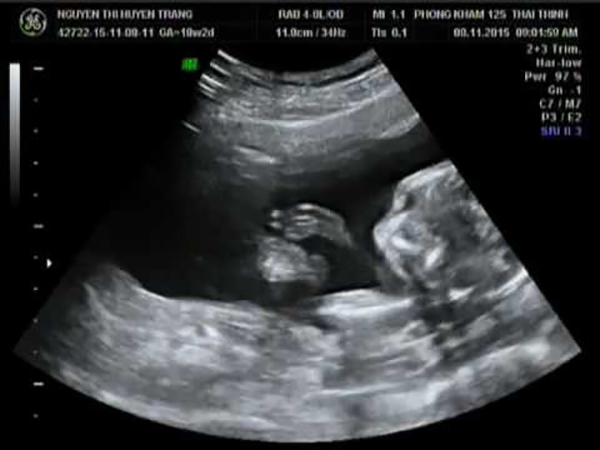

Đây là phương pháp siêu âm được xem và cổ tuy nhiên vẫn được sử dụng trong siêu âm thai nhi hiện nay. Tuy nhiên, với hình thức siêu âm 2D này thì thường chỉ áp dụng cho thai nhi dưới 20 tuần tuổi. Để có thể kiểm tra vị trí của thai, hay những vấn đề bất thường có trên thai nhi.

Nhiều người cho rằng phải siêu âm hiện đại như 3D hay 4D thì mới có thể phát hiện được bé là nam hay nữ. Nhưng không các bác sĩ chuyên môn khẳng định rằng chỉ cần siêu âm loại 2D cũng có thể xác định được giới tính thai nhi rõ ràng nhất. Tuy nhiên, để nhìn rõ nhất thì phải ở thời điểm tuần thứ 15 trở lên.

Lợi ích tiếp theo khi lựa chọn hình thức siêu âm này đó chính là giúp các mẹ biết được số thai mình đang mang. Nhưng không phải lúc nào cũng đảm bảo sự chính xác. Bởi, có lẽ trong những tháng đầu tiên của tam cá nguyệt nếu mẹ mang song thai thì rất có thể ẩn sau tử cung của người mẹ. Tuy nhiên, khi siêu âm khoảng từ 15 tuần trở đi thì sẽ giúp các mẹ nắm bắt được chính xác và rõ ràng nhất.